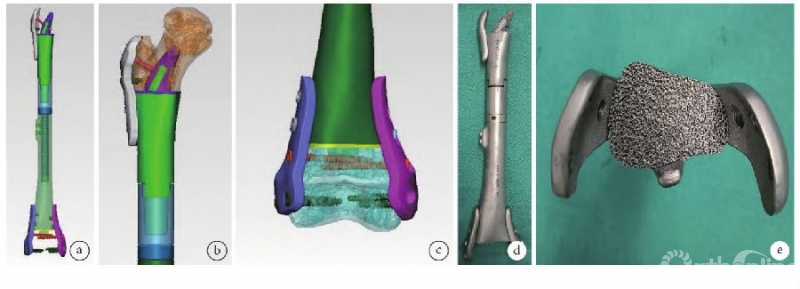

河南省肿瘤医院姚伟涛教授[5]团队通过回顾性研究评估了应用3D打印假体保留恶性骨肿瘤青少年患者关节面及骨骺的疗效,结果显示MSTS评分为19~28分,平均24.1分;获优8例,良2例。VAS评分为(0.9±1.0)分,较术前(5.9±1.0)分明显改善。